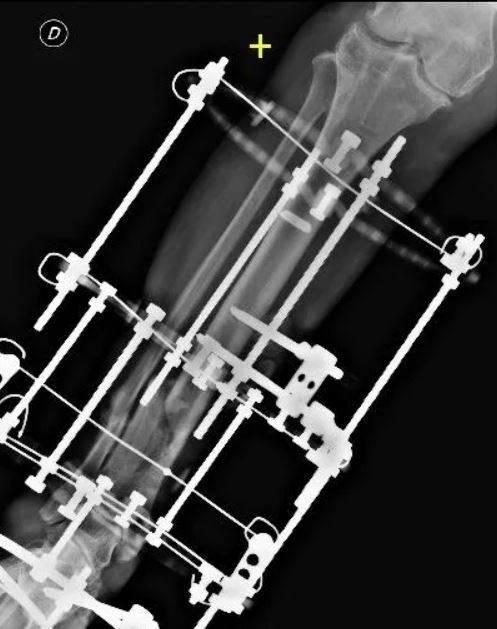

- External fixation: Orthopaedic surgeons apply an external device to the affected limb using steel wires and pins. This method is preferred for pseudoarthrosis without sufficient stability, infected cases, or those with bone loss.

Recent technical innovations have led to the development of more advanced external fixators that allow axial correction of deformities and bone healing, utilising osteogenic distraction. These fixators, called Hexapods, have transformed external fixation, making it simpler and easier for patients to manage. By gradually changing the length of 6-millimetre rods, the patient can autonomously correct axial deviations and lengthen the bone segment if necessary.